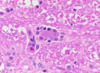

What is this structure and what is it’s function?

Choroid plexus

Function: produces CSF within the ventricles